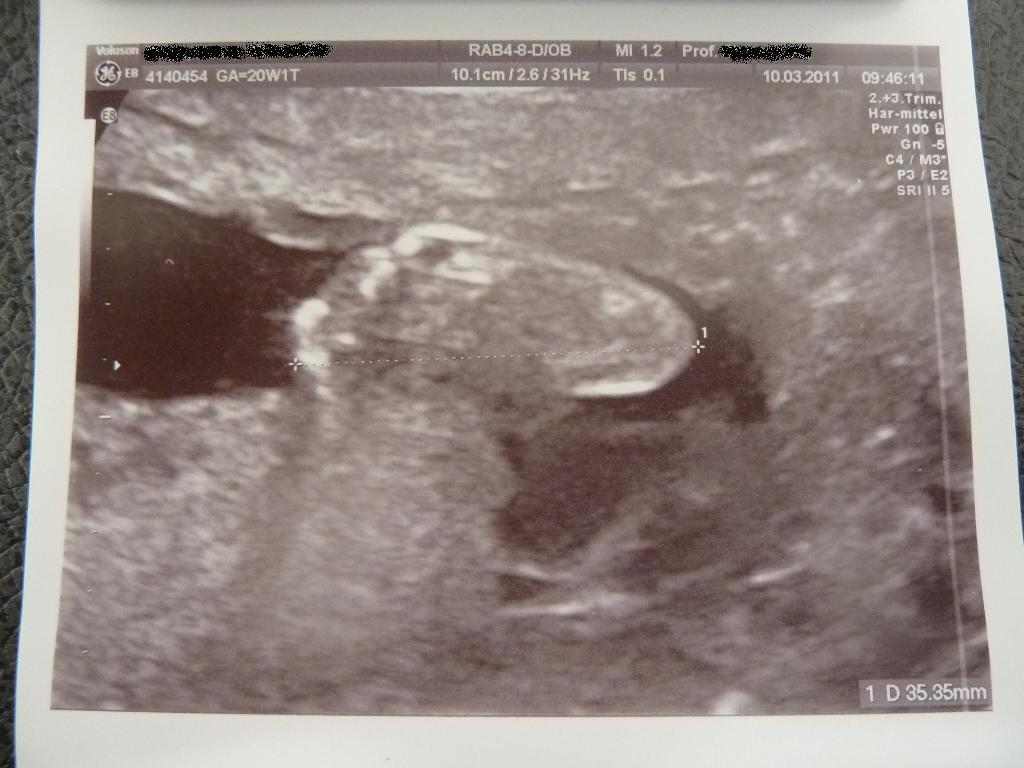

Anbei noch 2 Bildchen. Auf dem einen ist das Profil, nicht sehr gelungen aufgrund der Schwierigkeiten, die der Kleine beim Fotografieren macht. Auf dem anderen ist ein Füßchen zu sehen. Das Füßchen ist immerhin schon 3,5 cm lang –Wahnsinn, oder??????????